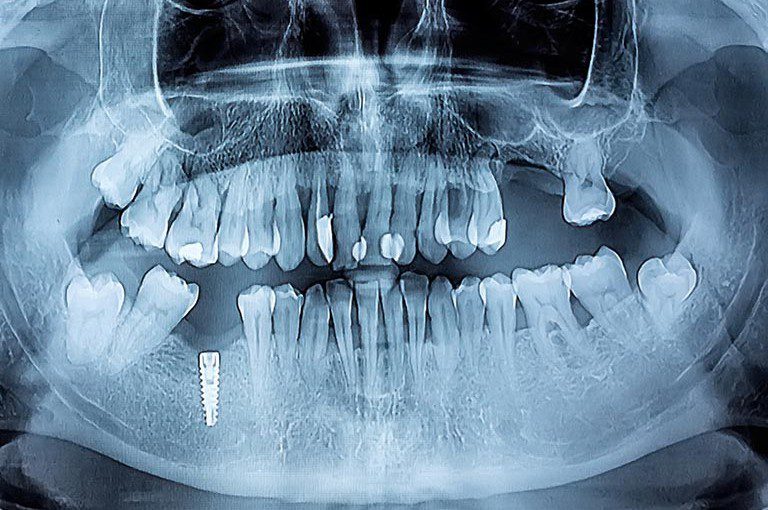

- Tecnología de diagnóstico 3D: En Grandental Móstoles, utilizamos estudios radiológicos avanzados para planificar cada caso con precisión milimétrica, asegurando que el implante se coloque en la posición óptima de acuerdo con la densidad ósea del paciente.

Realizamos una exploración exhaustiva y un estudio radiológico para evaluar la cantidad de hueso disponible y la salud general de las encías. Esta primera visita en Grandental es gratuita, permitiéndote resolver todas tus dudas sin compromiso.

Sí, hoy en día existen técnicas de regeneración ósea o elevación de seno maxilar que permiten colocar implantes incluso en casos de pérdida ósea severa. Realizamos un estudio radiológico previo para determinar la viabilidad.